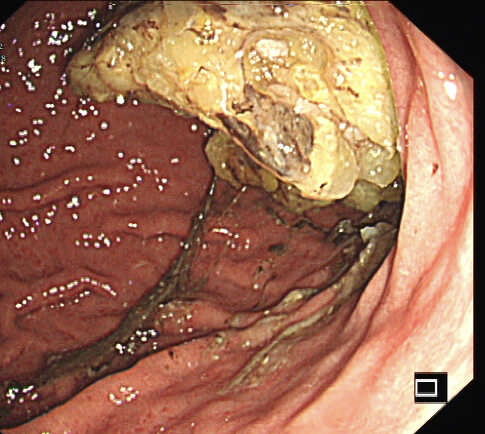

第二个病例,青年男性,也是突然腹痛,症状和第一个类似,首选腹部CT。

胃镜证实

同样治疗后痊愈出院